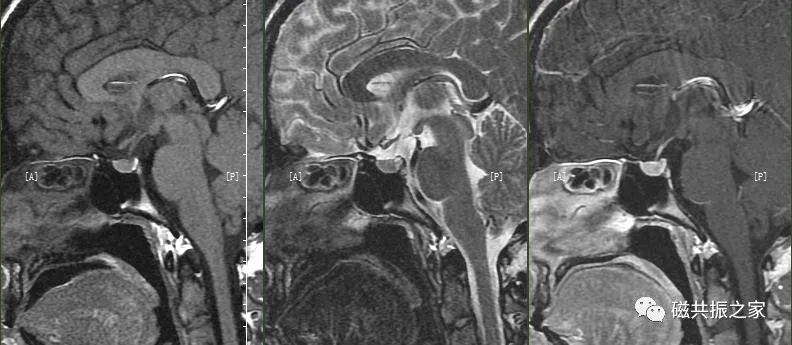

以冠状位和横断位作为参考定位。在横轴位上与大脑矢状裂平行;在冠状位上定位线与垂体柄平行,双侧对称扫描。FOV中心置于垂体位置,扫描范围包括整个垂体,根据病变大小调整范围,需包括整个病变范围。

矢状位是显示垂体前后叶最理想的方位。

以矢状位和横断位作为参考定位。在矢状位上定位线垂直于鞍底(或平行于垂体柄或垂直于垂体窝),在横断位上与大脑纵裂垂直,双侧对称扫描,扫描范围包括整个垂体,根据病变大小调整范围,需包括整个病变范围。

冠状位是观察垂体柄形态和测量垂体高度最理想的方位。

最理想的冠状位图像:同一层面视交叉、垂体柄和垂体均能清晰显示,共同组成“工”字结构。